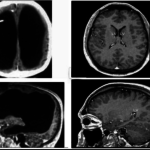

Doctor’s found that he had hydrocephalus as a child (when your brain is filled with fluids) so they decided to run some brain scans.

What they found was that the majority of his head was filled with fluid. Over time, the buildup caused his lateral ventricles to swell so much that his brain had been flattened to a thin sheet.

Doctors estimated that his brain mass had been reduced by at most 70%, affecting the areas in charge of motion, language, emotion, and, well, everything.

The doctors drained the fluid and while his brain is much smaller now, he is still a healthy individual with a normal life.